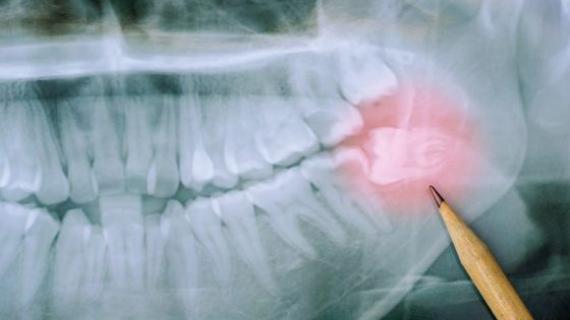

Пульпиты временных зубов в практике детского врача стоматолога: актуальность проблемы, особенности клиники и лечения

Распространенность пульпитов. Временные зубы играют важную роль в жизни растущего организма ребенка. Они оказывают влияние на развитие...